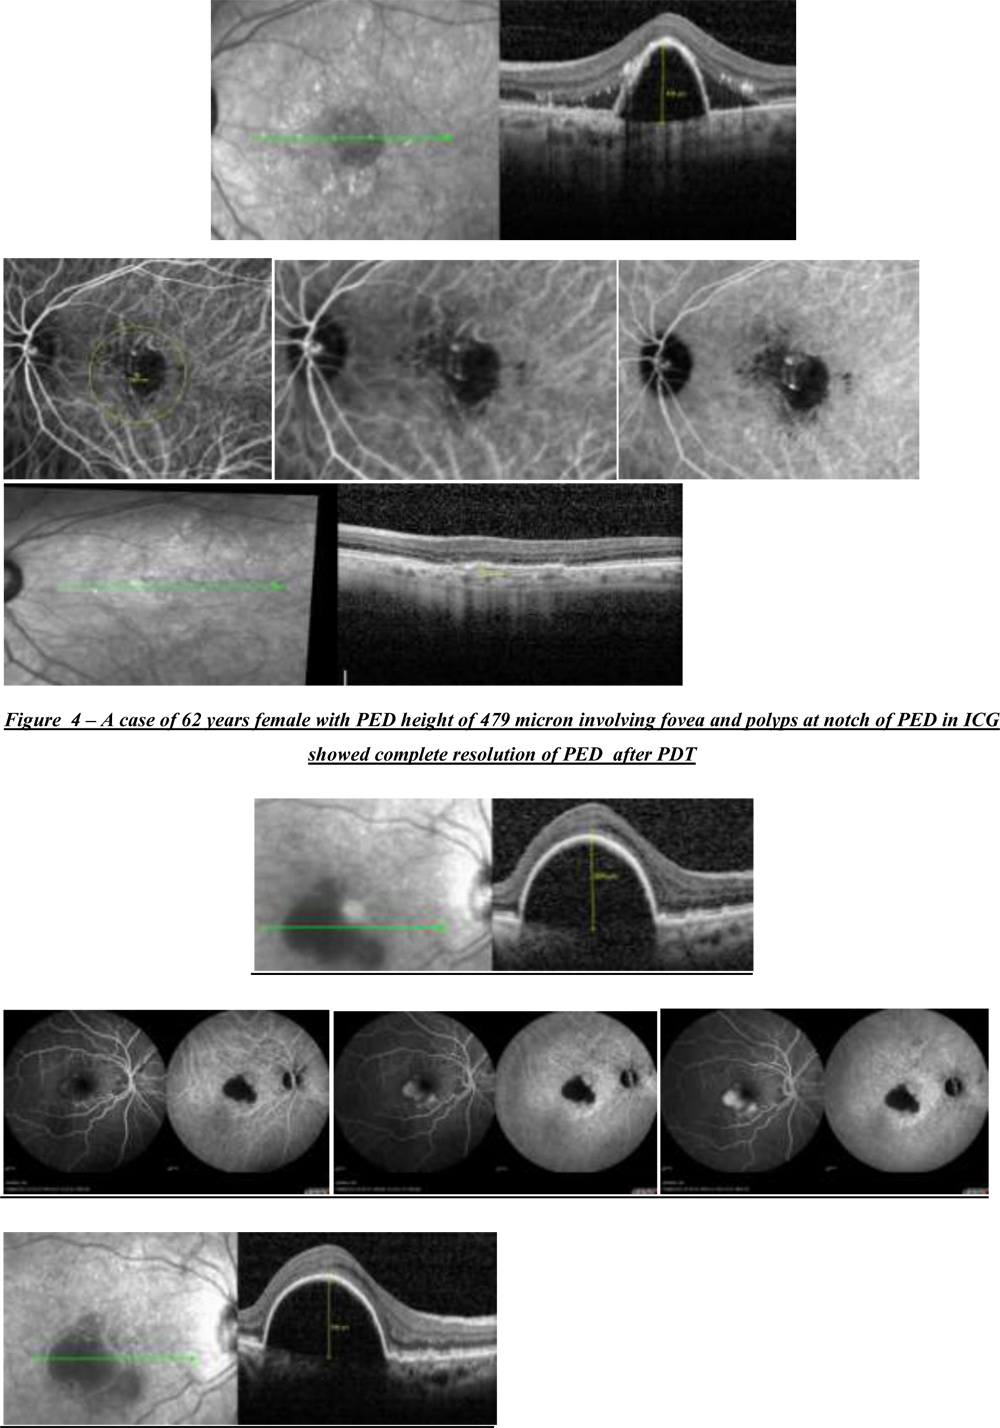

Figure 5 – A case of 75 years female with PED height of 625 microns showing features of occult CNVM on FFA like stippled Hyper Fluorescence with pooling of dye in PED which didn’t opt for any treatment and was observed

Figure 5 – A case of 75 years female with PED height of 625 microns showing features of occult CNVM on FFA like stippled Hyper Fluorescence with pooling of dye in PED which didn’t opt for any treatment and was observed